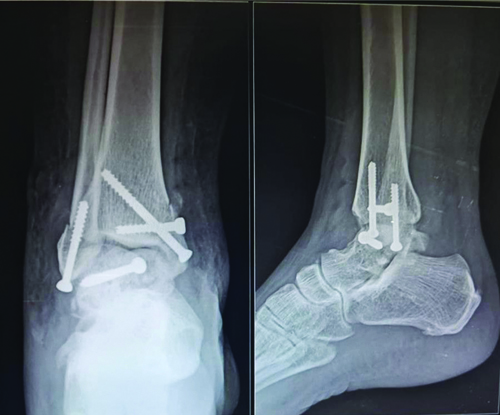

Postoperatively, the patient was advised against weight-bearing for six weeks [Table/Fig-5], progressing to full weight-bearing by 12 weeks. At the end of one year, there was a terminal limitation of ankle movements.

Postoperative radiograph of right ankle AP and lateral at six weeks postoperative.